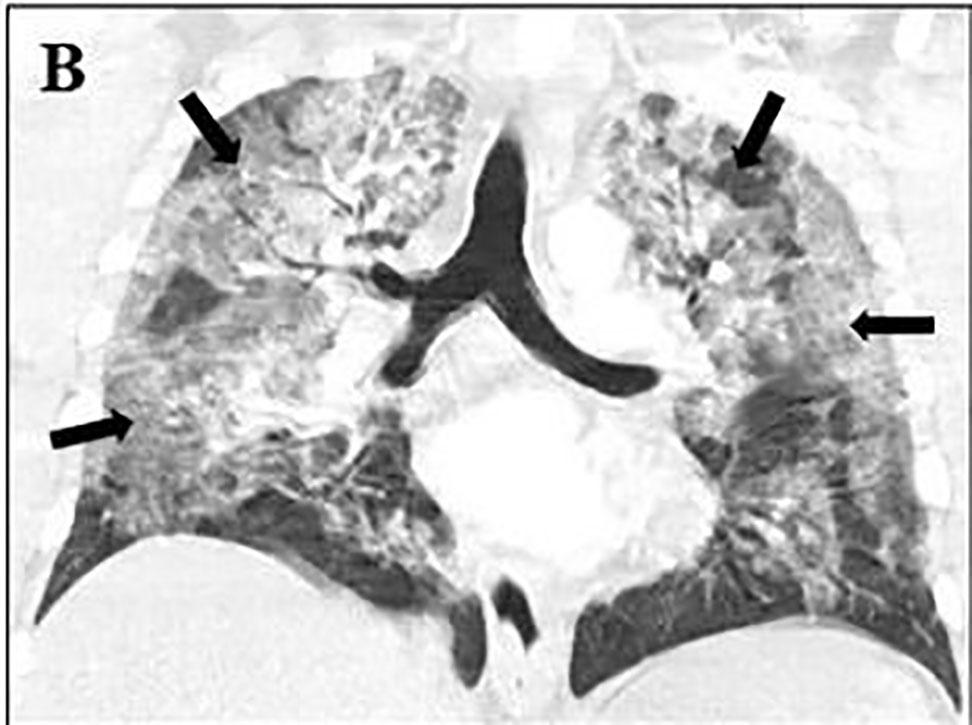

respiratory distress. No pulmonary embolism was present, but the CT did reveal extensive bilateral infiltrates consistent with a COVID-19 pneumonia (Image). After results had been obtained, a report from the transferring ED contained similar lab results, including a negative COVID-19 PCR. The patient was then admitted to the ICU for ongoing care.

Image. Computed tomography angiography of the chest. Black arrows indicate ground glass opacities. (A) Axial image showing bilateral central and peripheral ground-glass opacities. (B) Coronal image demonstrating bilateral ground-glass opacities in upper and lower lung fields.